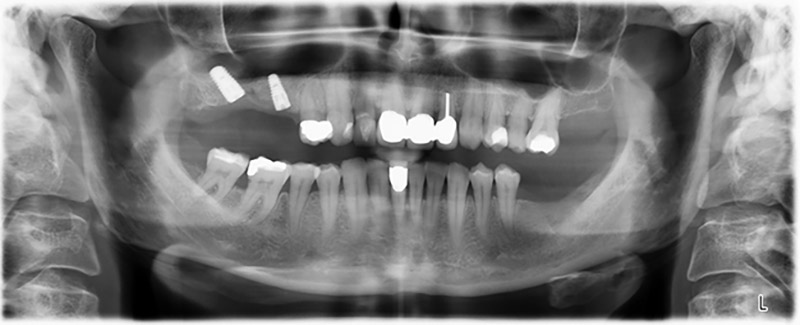

Etwa sechs Monate nach Extraktion der Zähne 16 und 14 wurde zur Planung und Risikominimierung eine digitale Volumentomografie (DVT, Planmeca) erstellt. Hierbei wurde deutlich, dass der Knochen sich nicht in der gewünschten Quantität regeneriert hat (Abb. 2 bis 7).